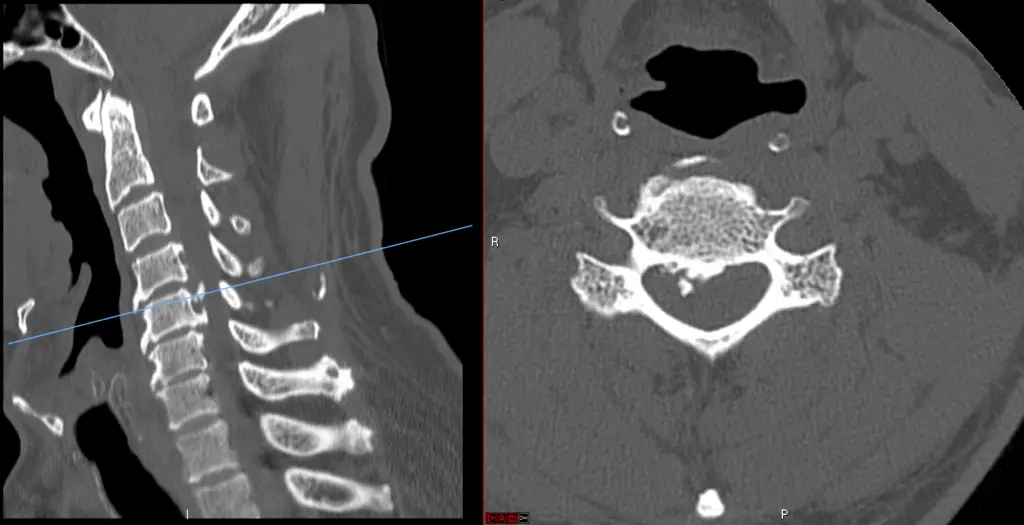

Cervical Corpectomy for Tumor

ACCF Preop 1024x507

Anterior Cervical Corpectomy and Fusion

c5 corpectomy ct